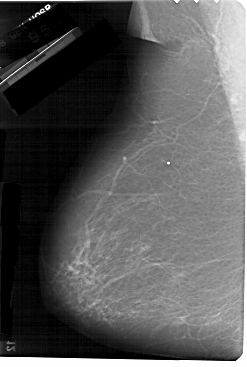

A_1267_1.LEFT_MLO

LEFT_MLO LINES 5491 PIXELS_PER_LINE 3691 BITS_PER_PIXEL 12 RESOLUTION 43.5 NON_OVERLAY